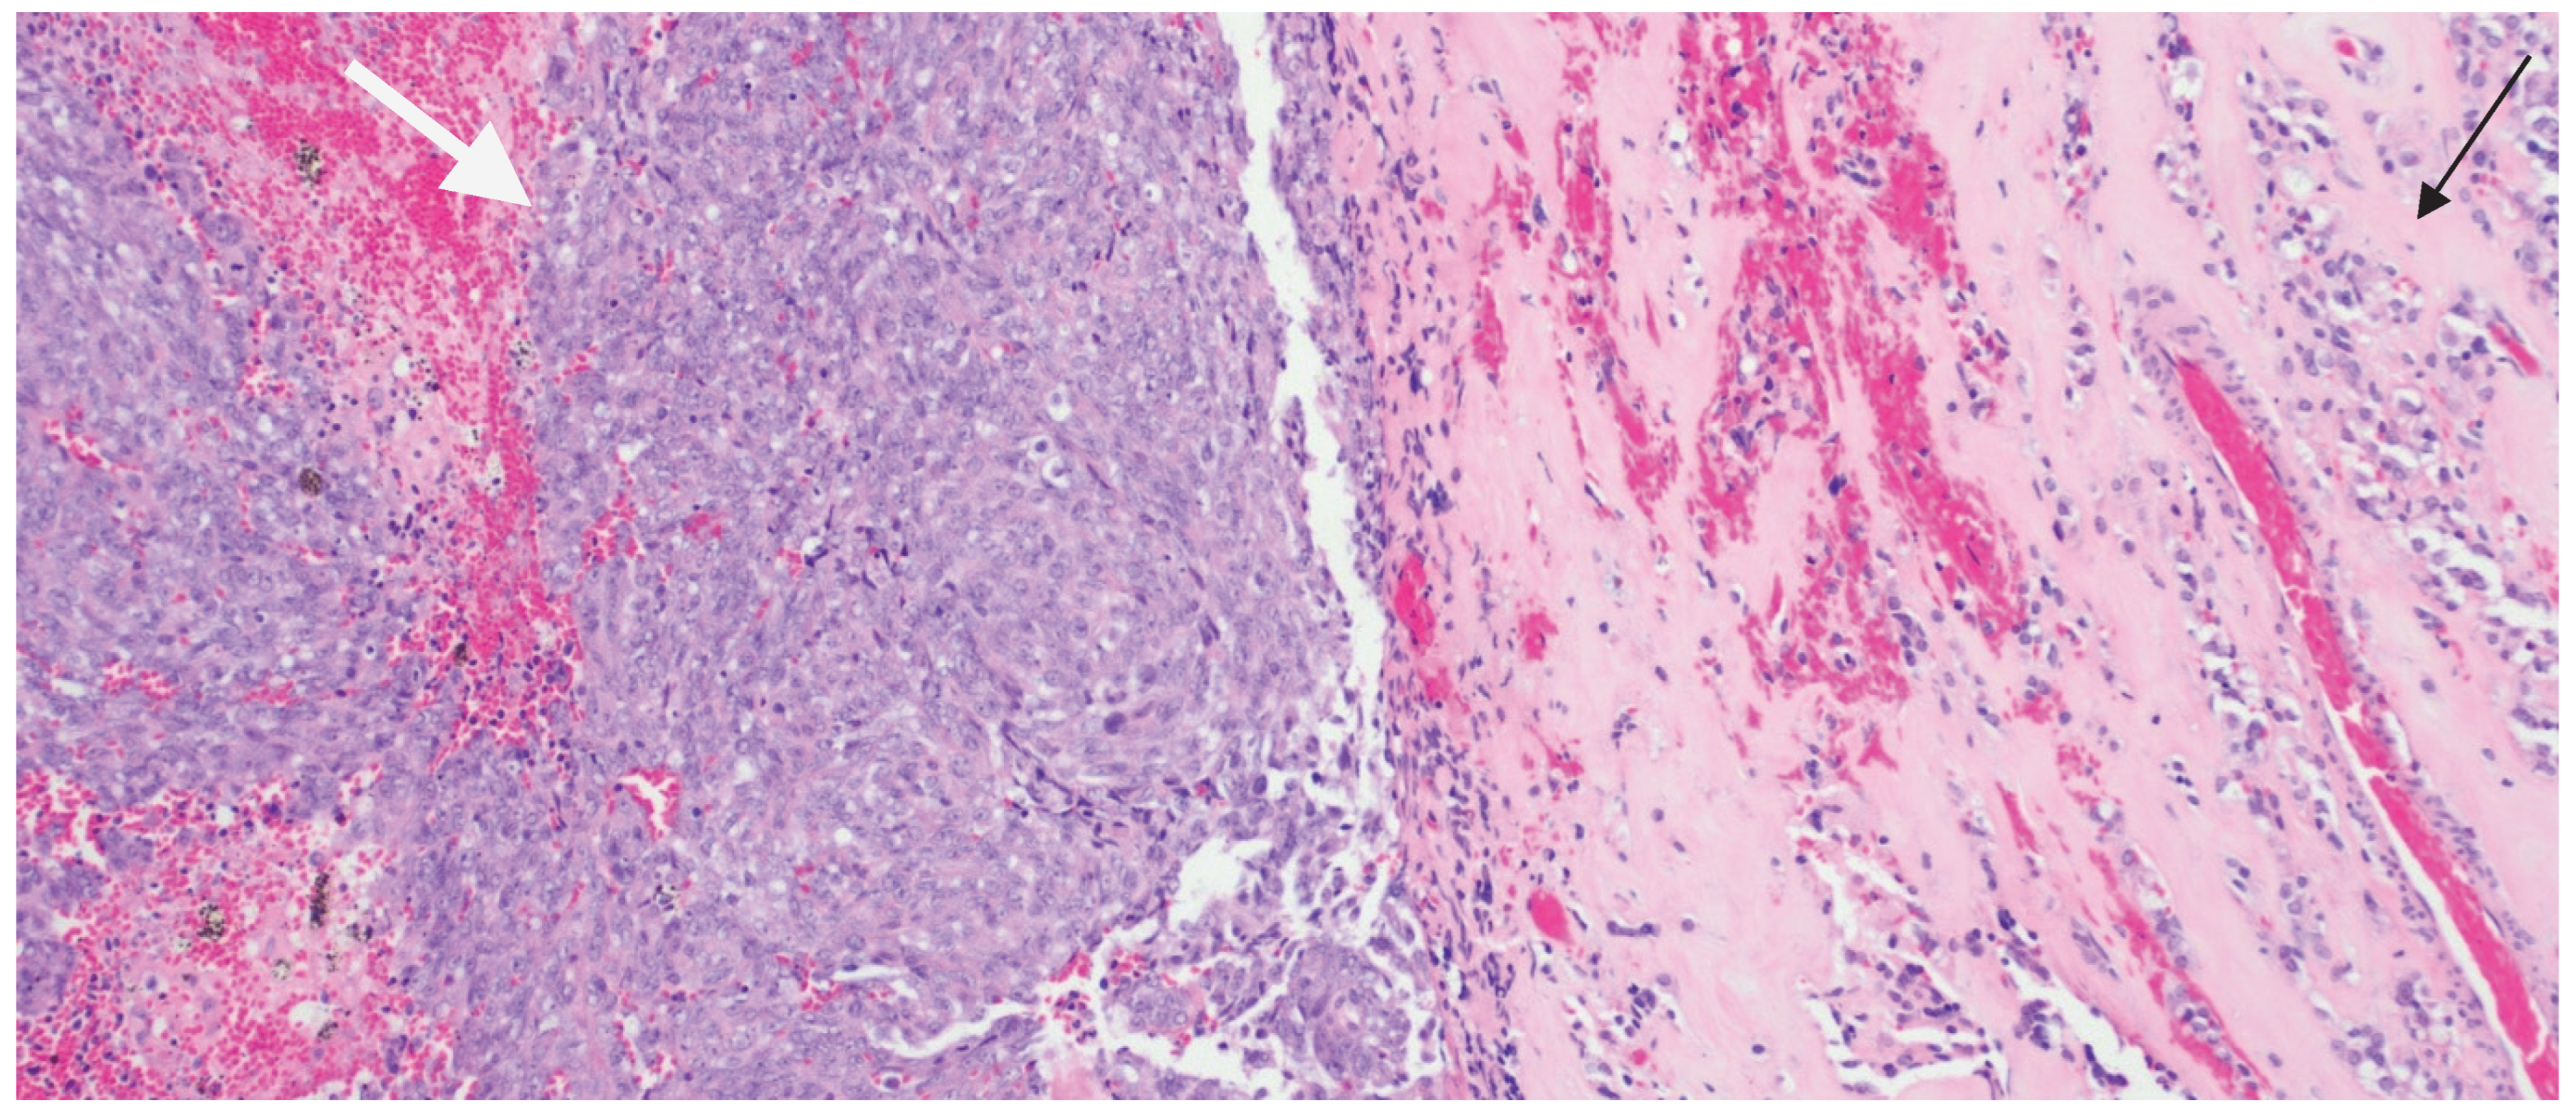

| Immunohistochemical Workup | Result | Notes |

|---|---|---|

| CK7, CK20, CK5/6, P40, D2-40, P63, BAP1, Desmin, Myogenin, STAT6, ER, PR, SOX10, S100, MiTF, Melan A, HMB45 | Negative | — |

| BRAF V600E, Synaptophysin, INSM1, TPIT, SF-1, LH, FSH, TSH, GH, ACTH | Negative | |

| AE1/AE3, CAM5.2, H3K27ME3 | Negative | |

| PIT1, Prolactin | Positive | PIT1 shown in Figure 3B |

| EMA | Focal Positive | EMA shown in Figure 4A |

| P53 | Positive (20%) | — |

| Ki-67 | High (60%) | High proliferative index (Figure 4B) |

| SSTR2 | Patchy Positive | Shown in Figure 4C |

| INI-1 | Positive | Loss of nuclear INI1 expression in ATRT cells (mutant); Figure 4D |

| E-cadherin | Retained | — |

| Reticulin stain | Positive | Highlights loss of reticulin investment in adenoma cells; |